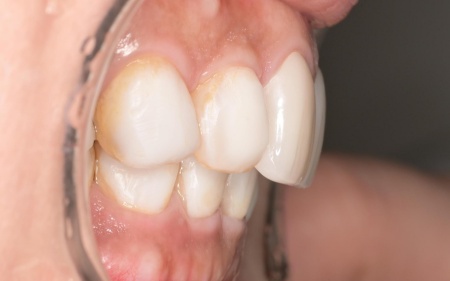

治療前

奥歯が噛み合わない状態になったことで、上前歯が前方に押し出され、出っ歯のようになっています。

また、下の歯は歯根だけが残る「残根」もあり、全体的に噛み合わせが不安定です。

さらに食いしばりの習慣があることから、残っている歯や顎関節に過度な負荷がかかっていると考えられます。